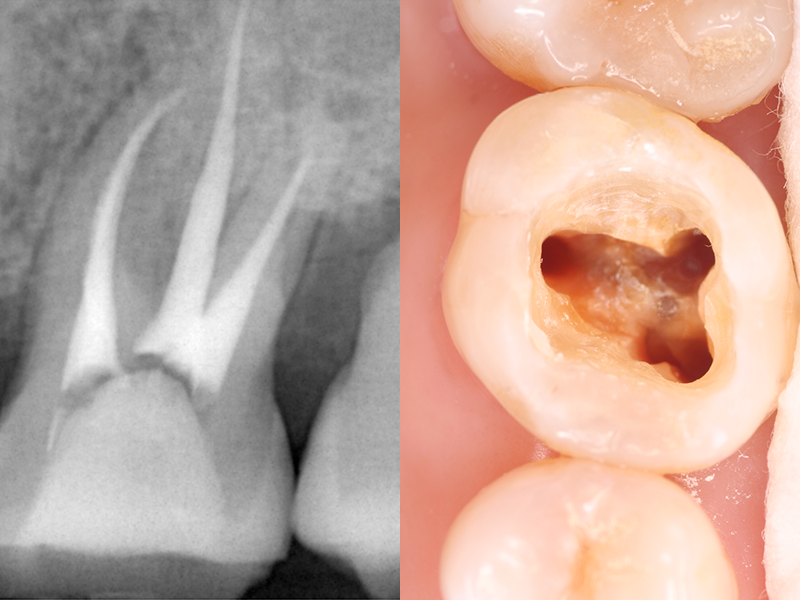

根管治療

根管治療は、歯の根の内部に入り込んだ細菌を取り除く、大切な治療です。歯の根の中は非常に細くて暗く、さらには複雑な形をしているため、従来は感覚に頼った処置になりがちでした。そのため、汚れや細菌が取り残され、治療後に再発してしまう場合も少なくありませんでした。

そこで当クリニックでは、拡大鏡を使用しながら目で確認しつつ、精密に処置を行なっています。

根の先までしっかりと確認することで、再発のリスクを抑え、治療の成功率を高めることができます。